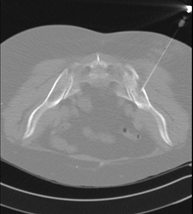

Prueba radiológica que consiste en obtener imágenes de los huesos maxilares de alta definición anatómica (piezas dentarias, trayecto del nervio dentario), mediante el empleo de un equipo de TC (Tomografía Computarizada). Indicaciones: estudio previo a la extracción dental, estudio previo a implantes, tumores, absceso. - TC Senos paranasales